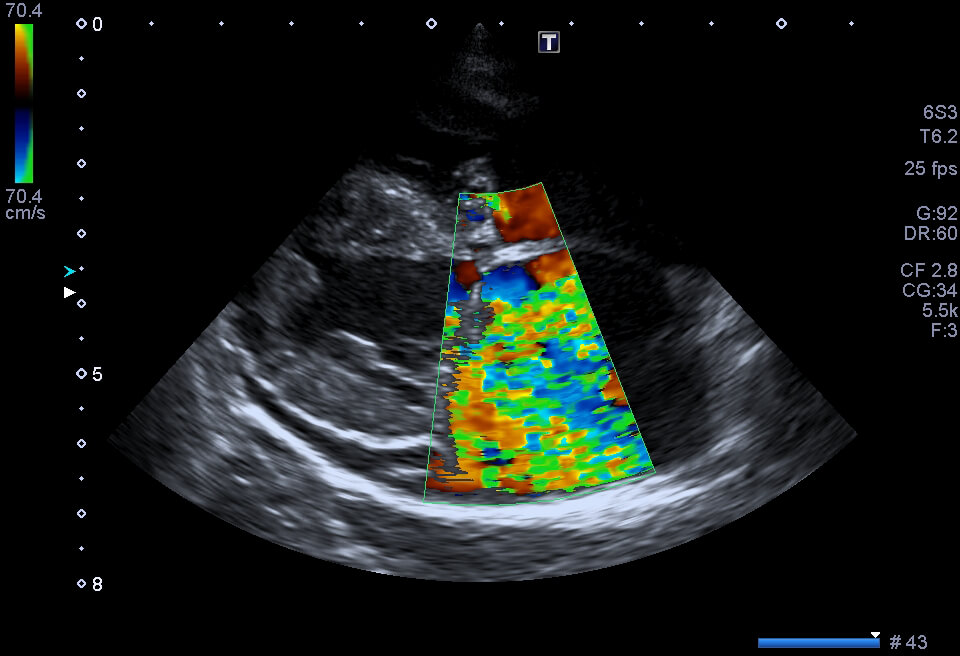

L’Ecocolordoppler cardiaco a riposo, o Ecocardiografia, è un esame non invasivo effettuato da uno specialista in Cardiologia, molto utile nella valutazione delle possibili patologie o malformazioni a carico del cuore. Il medico si serve dell’ausilio di un Ecografo, con sonde apposite, che consente di osservare e capire la forma, la dimensione, il movimento e la conformazione cardiaca.

Se eseguita correttamente, con un buono strumento e da un operatore esperto, essa consente di studiare con grande precisione i flussi interni al cuore, di individuare con esattezza la presenza di una trombosi (blocco di un vaso sanguigno provocato da un ammasso di globuli rossi/piastrine chiamato trombo), di diagnosticare le malattie delle valvole del cuore e di scoprire eventuali difetti congeniti (che cioè sono presenti sin dalla nascita).

Si tratta di un esame diagnostico basato sull’utilizzo di ultrasuoni, totalmente innocuo ed indolore per il paziente. Tramite l’ecografo il Cardiologo può visualizzare le camere cardiache, misurarne le dimensioni, valutare la funzionalità cardiaca e lo stato delle valvole.

Grazie alla funzione di ecocolordoppler cardiaco, si sfrutta l’effetto doppler per studiare la circolazione del sangue nel cuore.